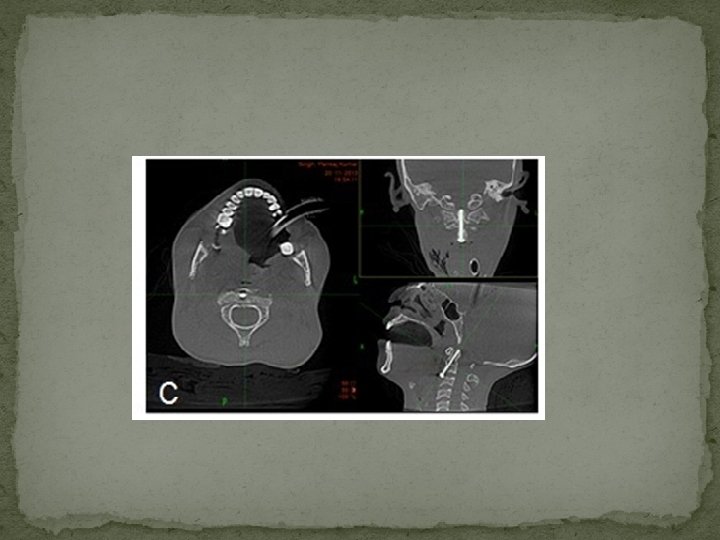

Screw failure salvaged with posterior fixation (Magerls Tech. + C 1 C 2 wiring) (D) Follow up CT scan at 3 month showing well fused fracture.